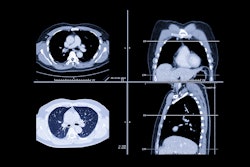

Clinically, PCCT is a valuable form of CT imaging when it comes to spatial resolution, dose reduction potential, increased contrast resolution, and multienergy imaging, but for most practices, the technology is a scarce resource, explained Adam Froemming, MD, professor of radiology at the Mayo Clinic in Rochester, MN.

Mayo placed PCCT in a high-throughput outpatient location that scans patients from early in the morning until late at night and serves the bulk of their thoracic outpatient practice. The hospital also positioned it for CT technologist training, which Froemming said was a significant struggle in the beginning.